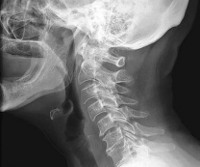

Шейный спондилоартроз. Дегенеративно - дистрофический процесс в мелких суставах шейного отдела позвоночника. Обычно поражает людей в возрасте 50-55 лет и старше. После травм, при некоторых заболеваниях и патологических состояниях признаки спондилоартроза могут выявляться у лиц молодого и среднего возраста. Заболевание проявляется ночными болями, болями при движениях и после статической нагрузки, утренней скованностью и ограничением движений. При сдавлении нервных корешков возникают неврологические нарушения. Диагноз уточняют при помощи рентгенографии, МРТ, радиоизотопного сканирования, УЗИ сосудов и других исследований. Лечение консервативное.

Для подтверждения диагноза назначают рентгенографию позвоночника, МРТ и КТ. Рентгенография шейного отдела информативна при наличии выраженных изменений в фасеточных суставах. КТ позвоночника более чувствительна и позволяет диагностировать спондилоартроз еще на начальных стадиях. На МРТ позвоночника видны сопутствующие изменения мягких тканей. Для оценки состояния мозгового кровообращения и исключения синдрома позвоночной артерии назначают допплерографию (УЗИ сосудов шеи и головы). При наличии неврологических нарушений больных направляют на консультацию к неврологу.